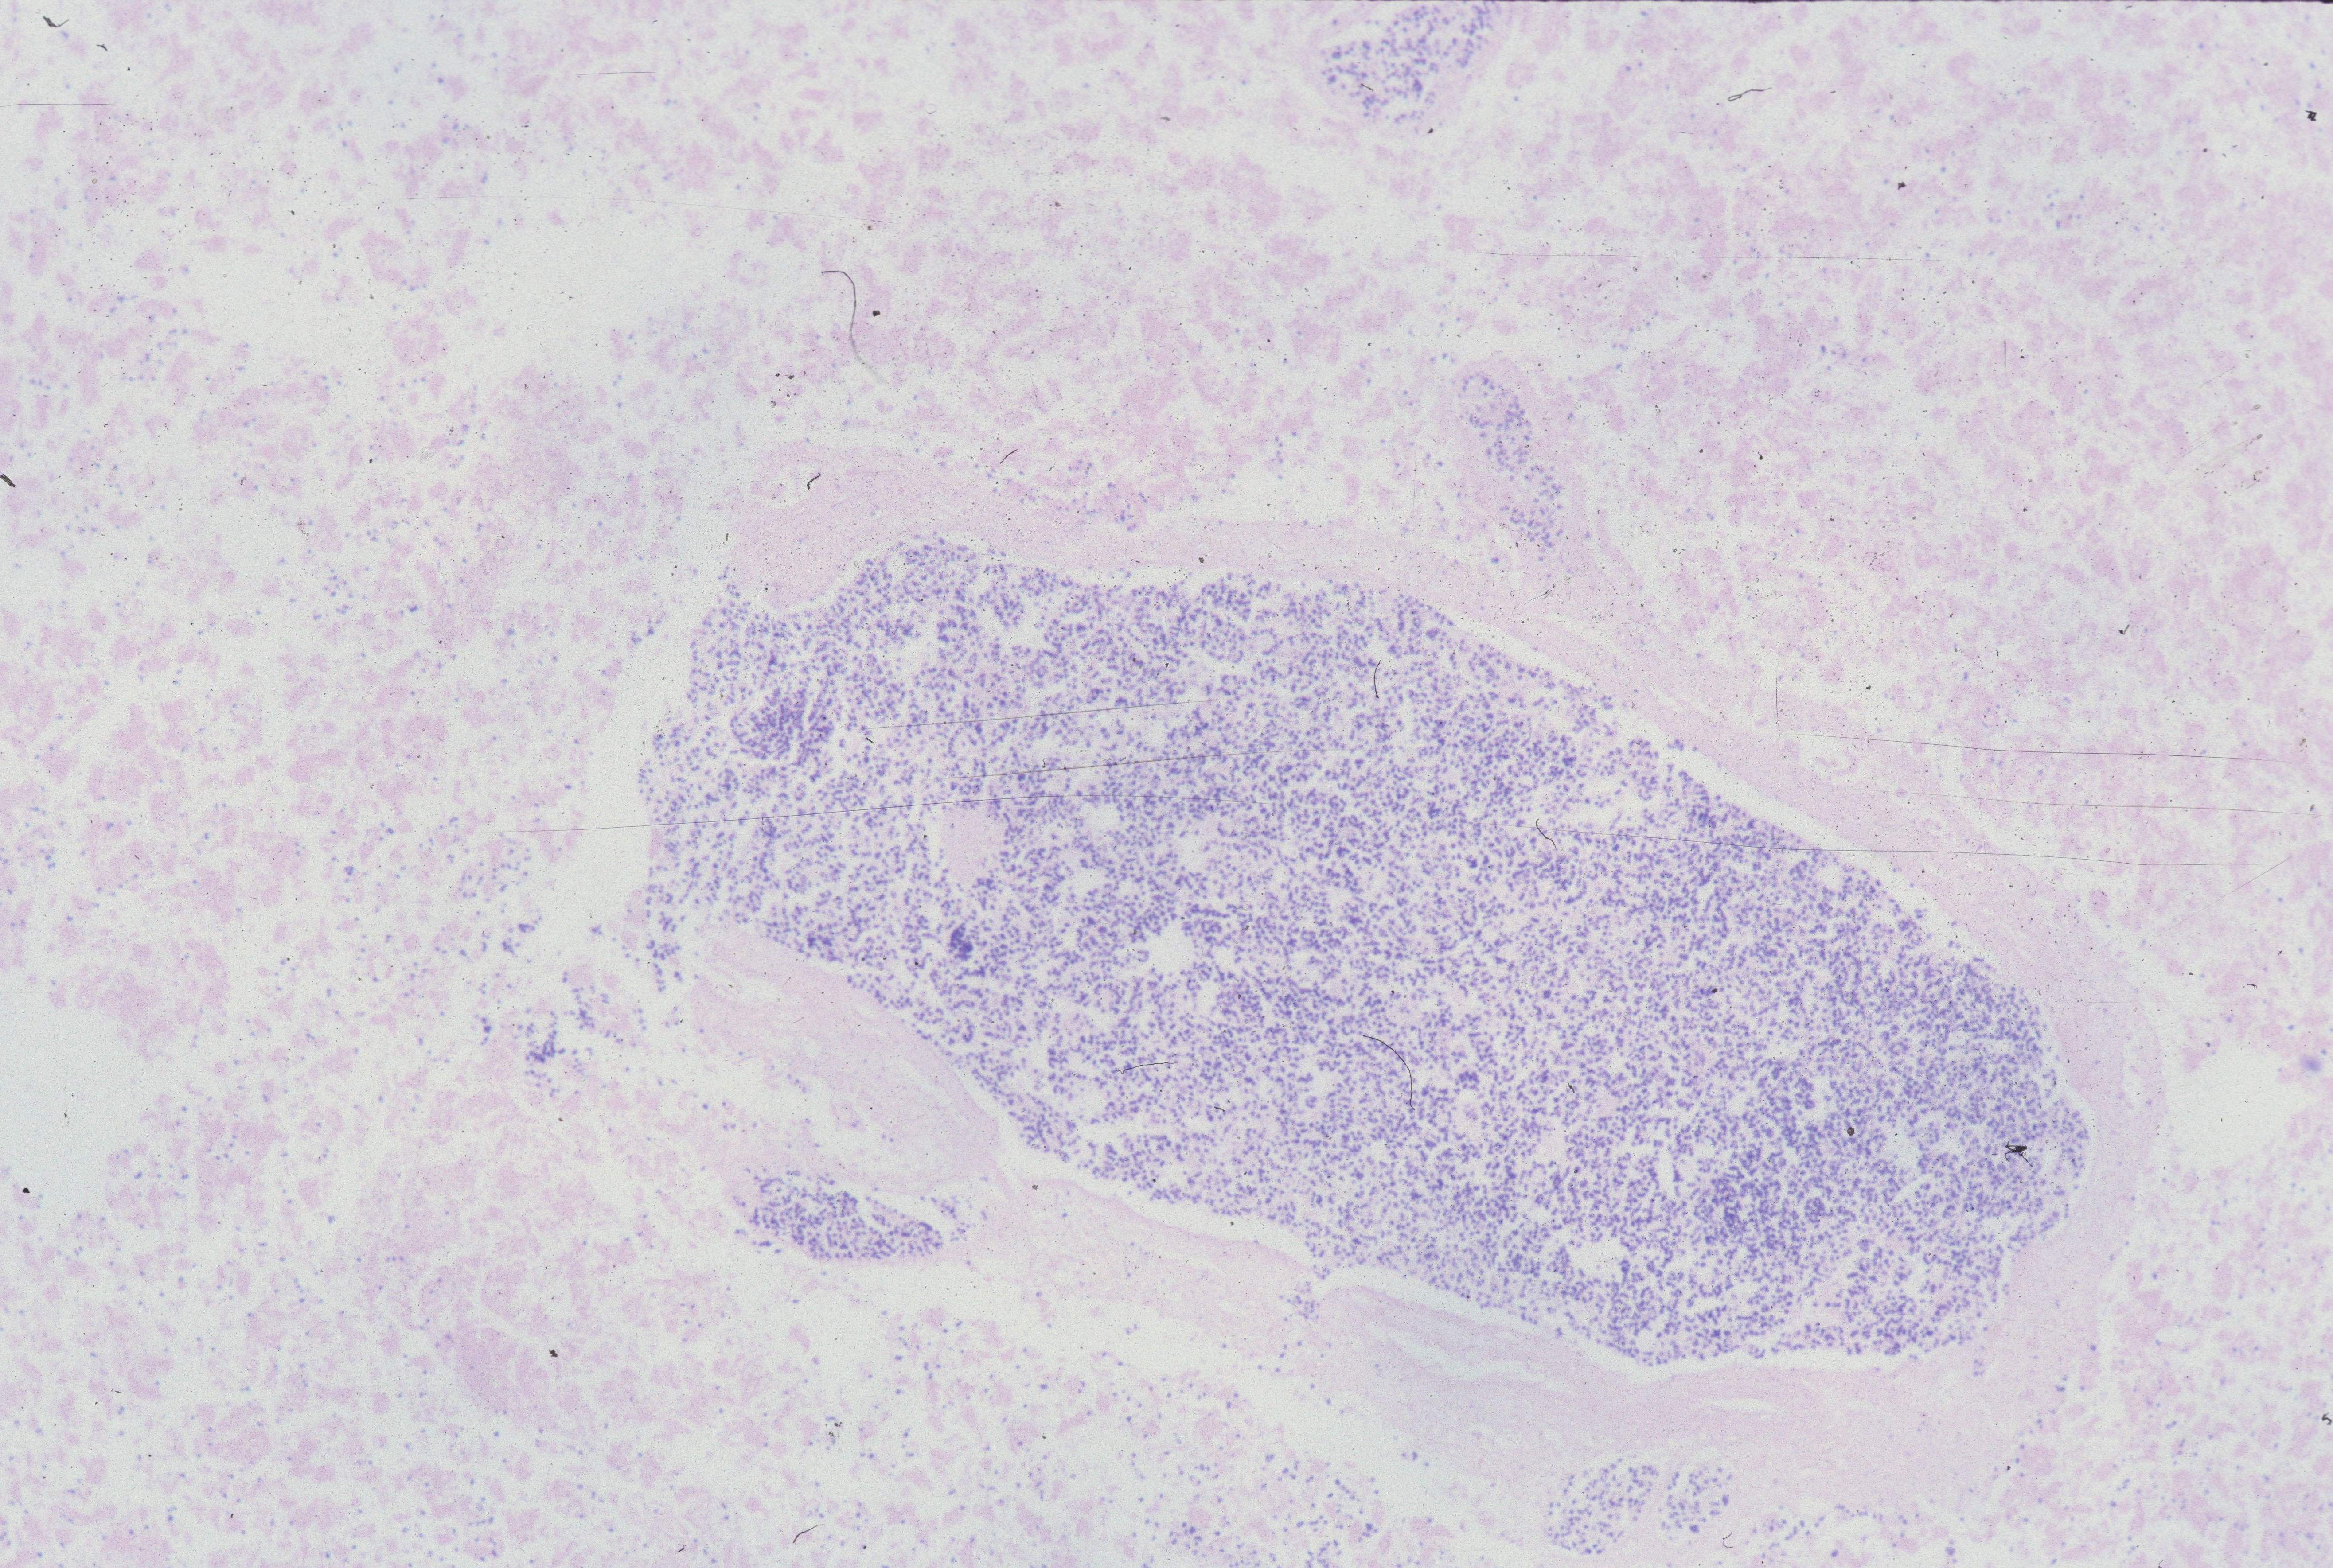

The loss of more than 1% of hepatocyte nuclear basophilia occurs in the window after 24 hours of postmortem retention (Fig 18)10.